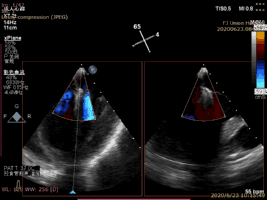

病例1術(shù)后二尖瓣反流為輕度